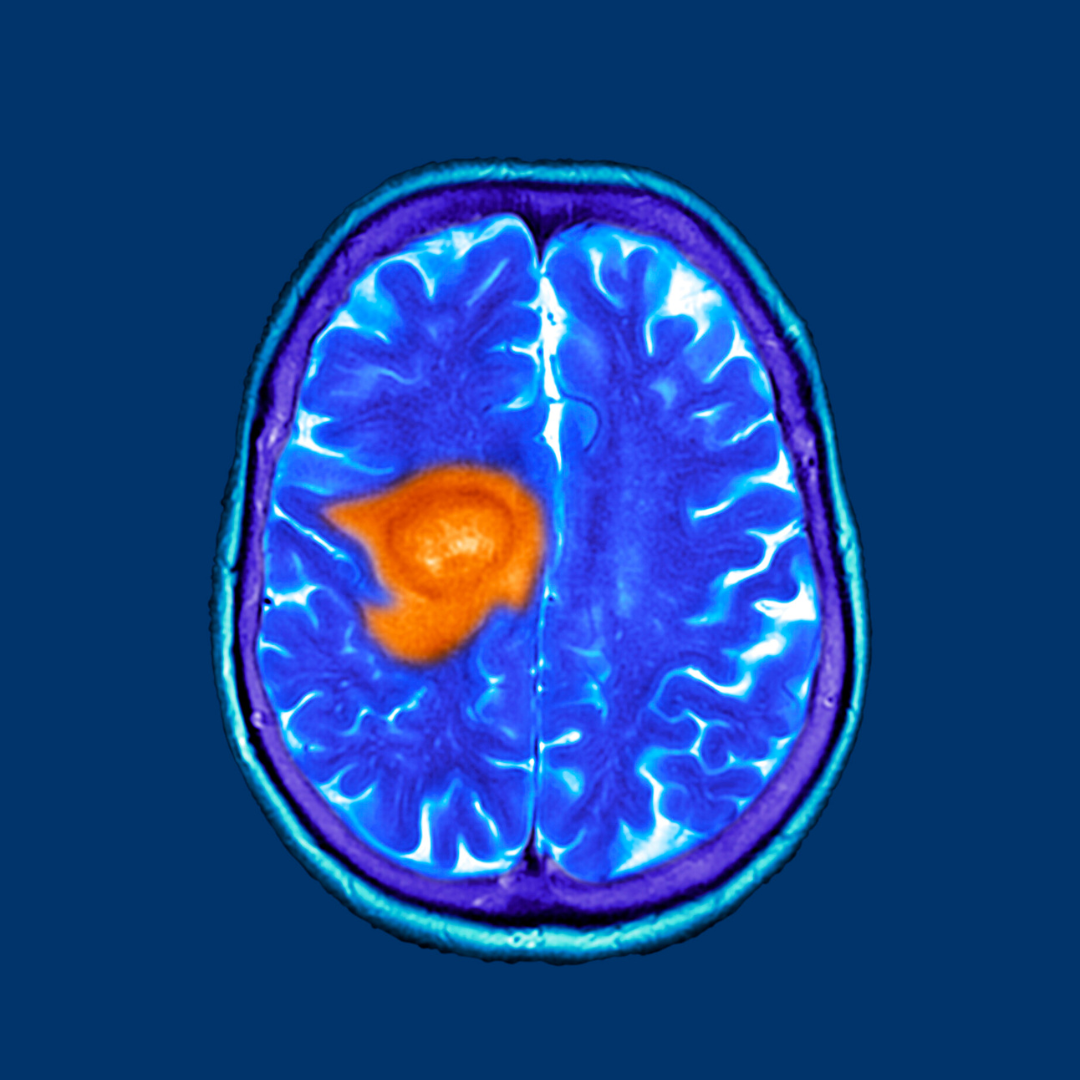

O diagnóstico de glioblastoma é desafiador e requer uma série de exames clínicos e de imagem. A ressonância magnética (RM) é o exame de escolha para avaliar a localização e a extensão do tumor. A confirmação geralmente é feita por meio de uma biópsia cerebral.

O glioblastoma é uma neoplasia maligna que se origina a partir das células gliais do cérebro. Sua nomenclatura, “glioblastoma multiforme,” reflete sua capacidade de assumir várias formas e é caracterizada por sua rápida progressão. É o tipo mais comum de tumor cerebral primário em adultos, representando aproximadamente 15% dos casos.